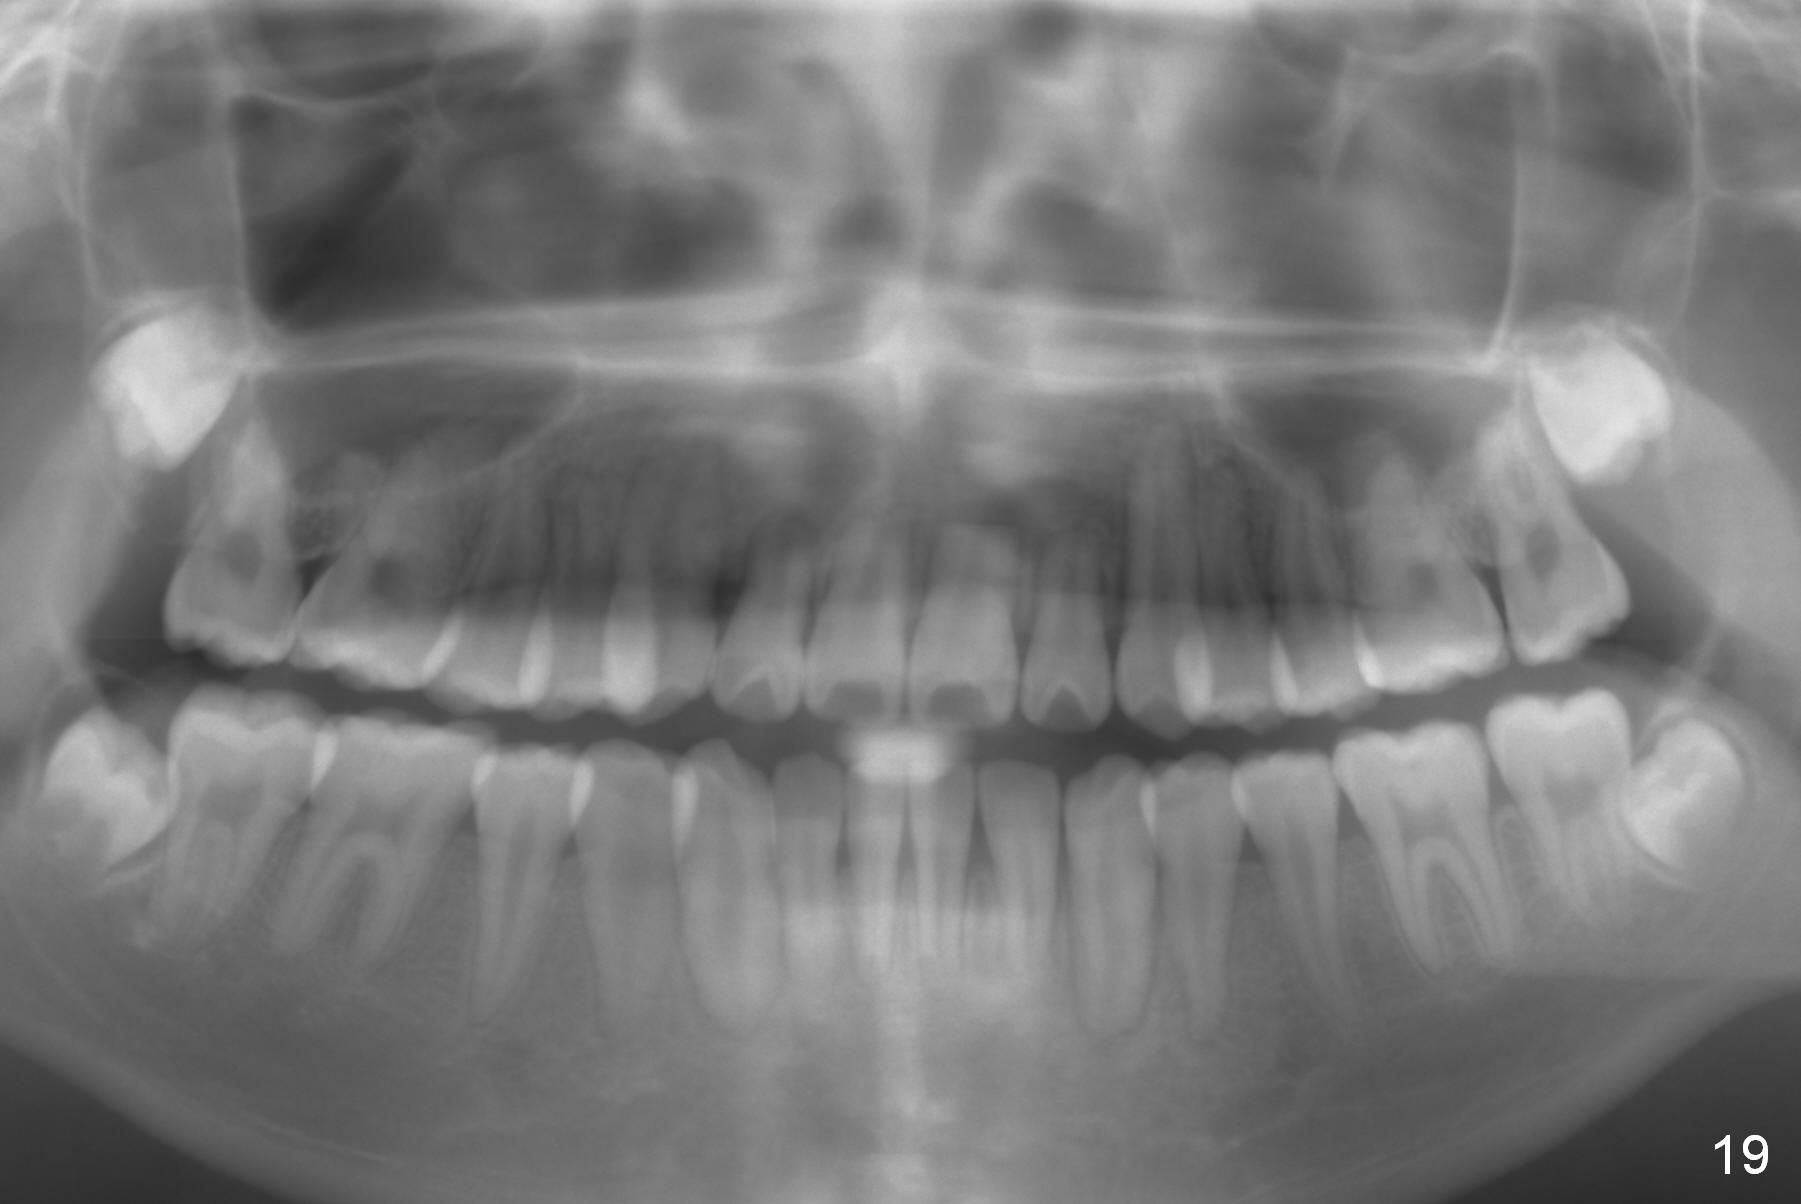

Non-extraction ortho takes 3 years 8 months to finish with shortening of #6-10, 22 and 27 roots (Fig.19) and compromised cosmetics (on the right column).